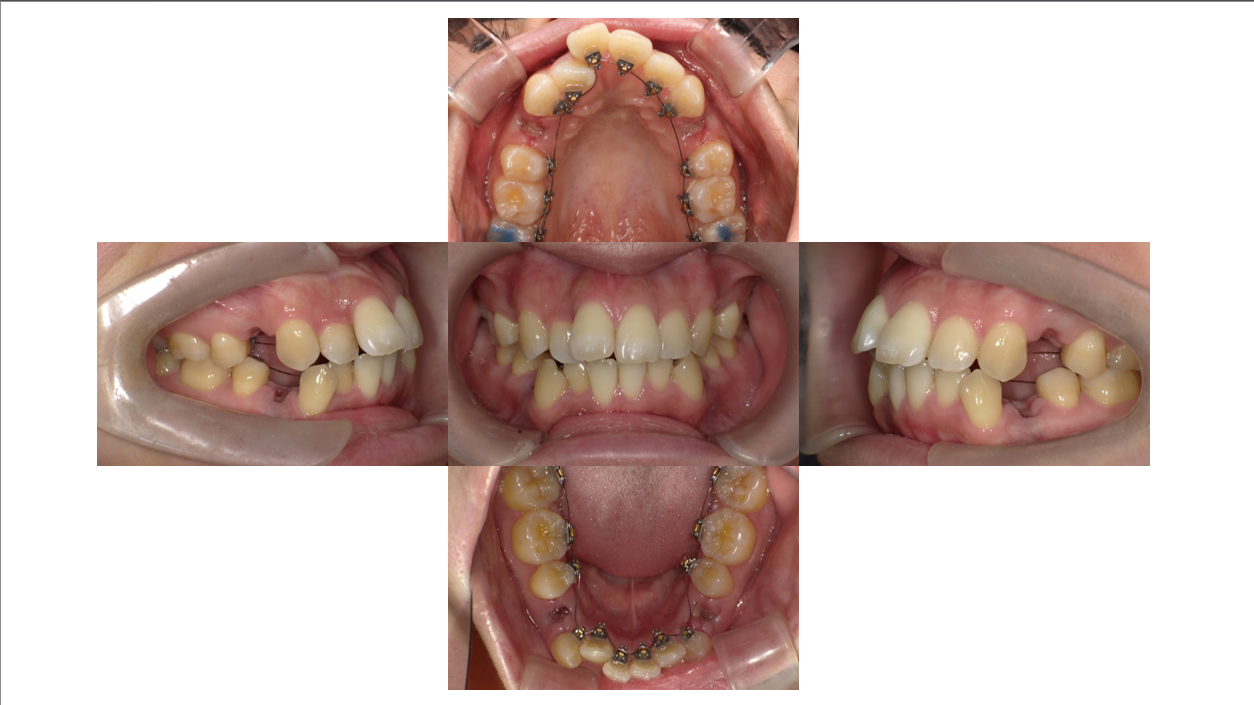

After

1年10か月

凸凹、出っ歯

前歯の位置もとても下がってきました。

抜歯の隙間がかなり小さくなってきました。

あと少し頑張っていきましょう。